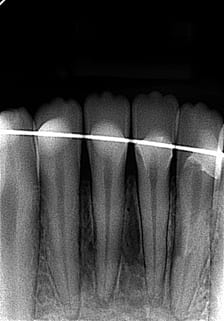

Quelque chose comme cela, qui doit rester souple. Fil fin en alliage nickel-titane et collage résine ou composite.

pr la contention le fil odf est très bien + compos

voir photo post au dessus